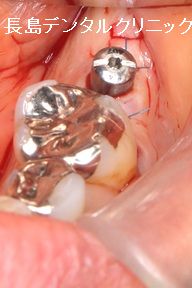

左下奥歯に(赤い矢印)1本インプラントを埋入した症例です。イン

プラントを埋入し歯茎を閉じる際歯茎を閉じる方法を2回法、そして

インプラントにアバットを装着しそのアバットが歯茎の外に出ている

場合を1回法と呼んでいます。今回の症例は3枚目の画像を見ていた

だくと、シルバーの器具が歯茎の外に出た状態で縫合を終えているの

がわかると思います。これが1回法です。1回法と2回法どちらが優